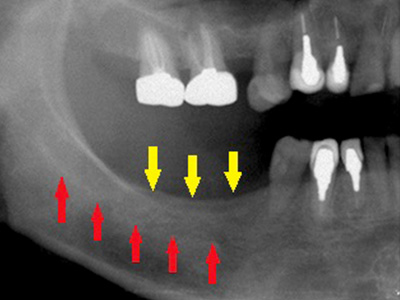

40代女性。上顎前歯を抜歯、虫歯と歯槽膿漏の状態が悪く、抜歯されたのですが、歯を支える歯槽骨が大きく吸収されてしまっていました(黄色矢印)。

インプラント治療を希望されていたのですが、下顎骨の中を通る神経(赤色矢印)が近接していて、骨が不足しているためインプラントの埋入が困難な状況でした。 -